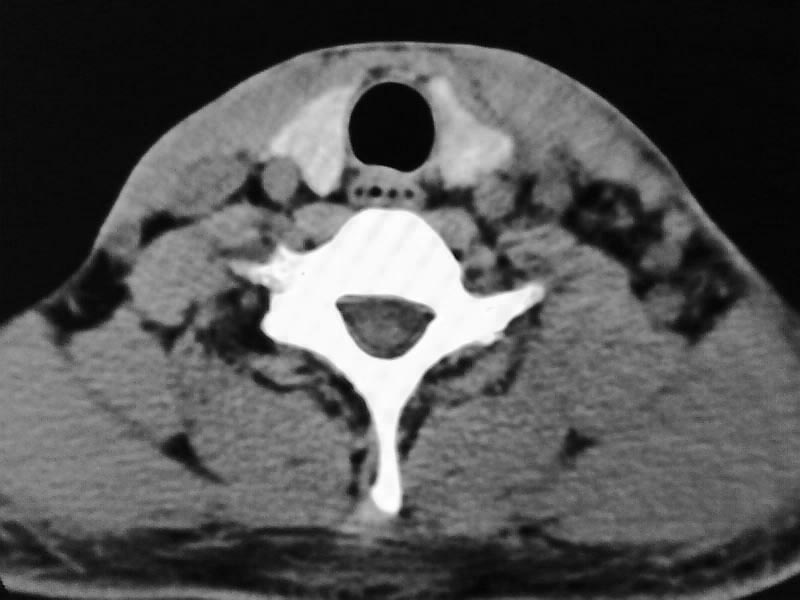

以下是引用余辉在2009-5-3 11:36:00的发言:[br]左侧胸锁乳突肌下方不规则肿物影,边界不清,内部密度不均,左侧颈外侧区脂肪增多,多发淋巴结肿大,考虑淋巴或神经来源肿瘤可能性大,不除外淋巴结炎,肌源性肿瘤及增生性肌炎等,活检